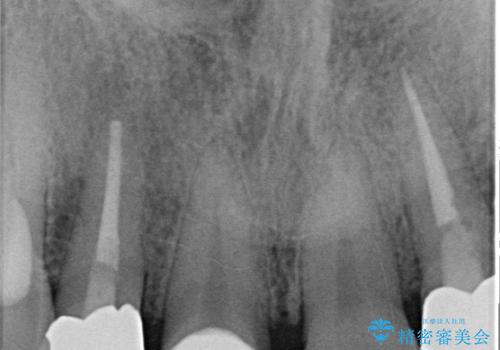

- 主訴:詰め物が取れた。

2日前に詰め物が取れ来院されました。中で虫歯が広がっている状態でした。歯科の治療が少し怖いとのことで静脈内鎮静を希望されました。

隣と同じように白くしたい、再治療を減らしたいとのことで、セラミッククラウン(スペシャル)で治療することとなりました。

治療回数を減らしたかったため、虫歯をとり形成を行い仮歯への置き換えとともに型どりを行いました。